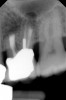

Clinical procedure: If apical bone loss is present (Figure 1) a collagen/gelatin sponge (eg, Gelfoam®, Pfizer Inc., www.pfizer.com) can be placed apically so that the MTA can be delivered to the desired working length. (Any other surgical resorbable sponge would also work, such as OraPlug® [Salvin Dental Specialties, www.salvin.com], Surgifoam® [Midwest Dental, www.mwdental.com], or Surgispon® [Aegis Lifesciences, www.surgispon.com]). This is done by taking a small piece (2 mm x 2 mm) of the resorbable sponge and pushing it down to and through the root apex with an endodontic file. Once this is done, MTA is packed down the canal with a custom-fitted cone. The clinician can use a rubber stopper on the gutta-percha cone to know the exact length of MTA placed in the apical third (Figure 2). Once the apical third is sealed with 3 mm to 5 mm of MTA, the remaining coronal canal space can be back-filled using a warm gutta-percha technique (Figure 3).

Fig 1. Preoperative radiograph showing apical bone loss.

Figure 1